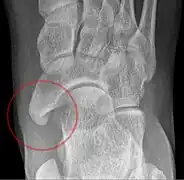

Radiological images

To diagnose accessory navicular syndrome, the foot and ankle surgeon will ask about symptoms and examine the foot, looking for skin irritation or swelling. The doctor may press on the bony prominence to assess the area for discomfort. Foot structure, muscle strength, joint motion and the way the patient walks may also be evaluated. X-rays are usually ordered to confirm the diagnosis. If there is ongoing pain or inflammation, an MRI or other advanced imaging tests may be used to further evaluate the condition.[5]

The Geist classification divides the accessory navicular bones into three types.[3]

• Type 2: Triangular or heart-shaped ossicle measuring up to 12 mm, which represents a secondary ossification center connected to the navicular tuberosity by a 1–2 mm layer of fibrocartilage or hyaline cartilage. Portions of the posterior tibialis tendon sometimes insert onto the accessory ossicle, which can cause dysfunction, and therefore, symptoms.